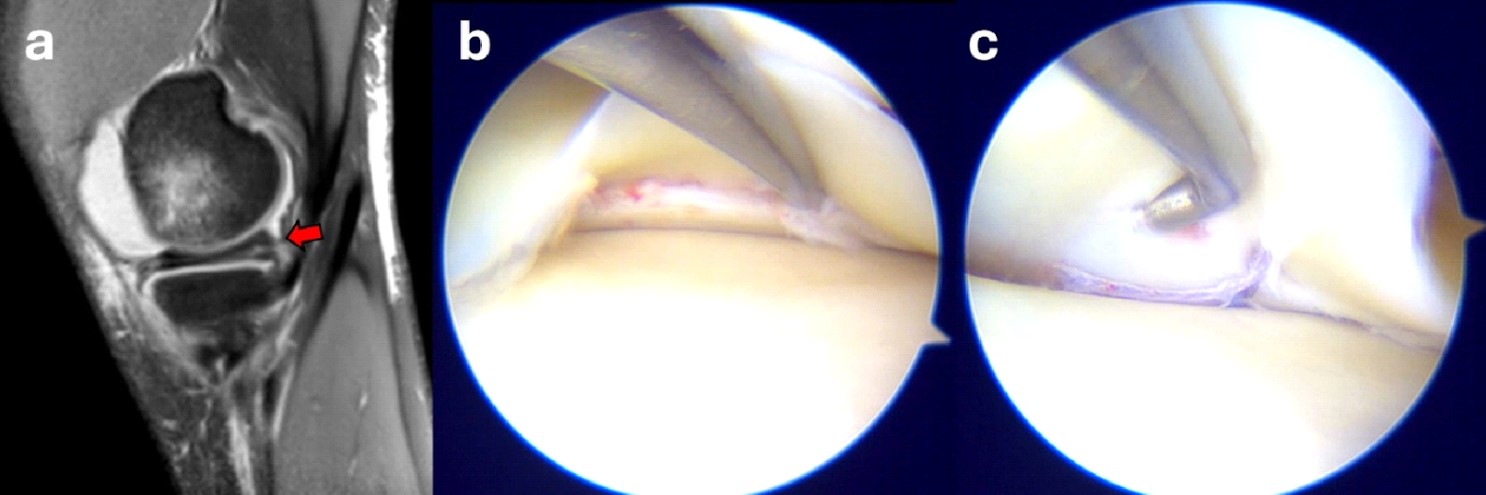

Conventional X-rays are often used as the initial diagnostic tool to identify fractures. CT scan is generally used in ambiguous cases and to better determine the degree of displacement4 (Figure 1). Based on that, the fracture can be classified according to the Meyers and McKeever’s classification in: Type I: minimally/nondisplaced fragment (< 3 mm); Type II: anterior elevation of the fragment; Type III: complete separation of the fragment (Type IIIa involves a small portion of the eminence; Type IIIb involves the majority of the eminence); Type 4: comminuted avulsion or rotation of the fracture fragment5. Alternatively, Green et al6 highlight the key role of MRI in the assessment of tibial eminence fracture because of the possibility to identify associated injuries such as meniscal tears (Figure 2) or ligamentous damage6,7. In our experience, additional soft tissue injuries such as meniscal entrapment or ACL injuries are identified alongside the fracture in a substantial number of cases8-10. The treatment approach depends on the severity of the fracture, with nondisplaced fractures often treated conservatively with immobilization in extension for 4-6 weeks11. However, in cases where there is a significant displacement, surgical intervention is typically required to prevent long-term instability, nonunion, or malunion12. Different surgical approaches have been proposed to manage tibial avulsion fractures. Among them, Arthroscopic Reduction and Internal Fixation (ARIF) has gained increasing preference over open techniques due to its minimally invasive nature, fast recovery times, and limited complications.

Figure 2. Sagittal MRI images showing a lesion of the medial meniscus posterior horn (red arrow) in combination with anterior tibial eminence fracture (a); arthroscopic view before (b) and after (c) all-inside meniscal repair.